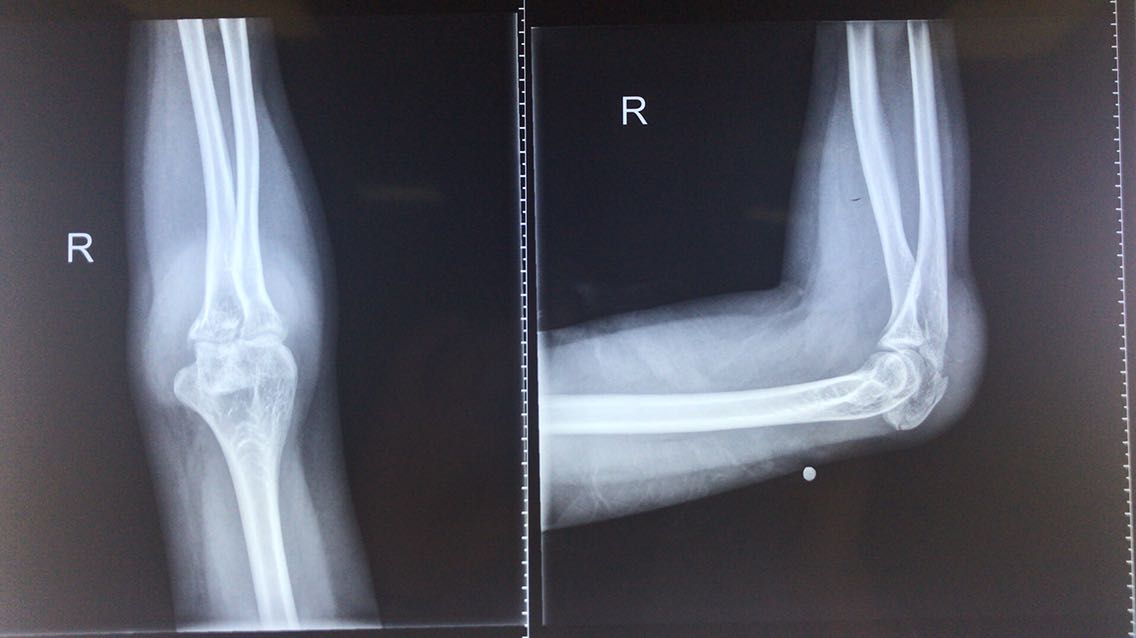

患者女性,35岁。 主诉:摔倒后致右肘关节疼痛伴活动受限5小时。 现病史:5小时前患者骑自行车时不慎摔倒致右肘着地,伤后即感右肘部疼痛,伴右前臂无力,无意识障碍等不适。遂就诊于我院急诊科,查右肘关节正侧位X片示:右尺骨鹰嘴粉碎性骨折。急诊遂以“右尺骨鹰嘴粉碎性骨折”收入我科。 既往史无特殊。

查体:右肘明显肿胀,局部可见皮肤擦伤,右尺骨鹰嘴处可触及骨擦音和骨擦感,局部压痛明显。右肘关节因疼痛明显活动受限。 辅助检查: 右肘关节正侧位X片示:右尺骨鹰嘴粉碎性骨折。